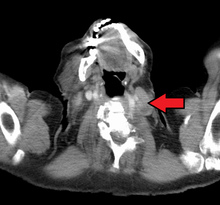

Virchow's node (or signal node) is a lymph node in the left supraclavicular fossa (the area above the left clavicle). It takes its supply from lymph vessels in the abdominal cavity. The finding of an enlarged, hard node (also referred to as Troisier's sign) has long been regarded as strongly indicative of the presence of cancer in the abdomen, specifically gastric cancer, that has spread through the lymph vessels. It is sometimes called the signal node or sentinel node for the same reason. Despite this, the concept is not directly related to the sentinel node procedure sometimes used in cancer surgery, and it is also unrelated to the "sentinel gland" of the greater omentum.

Malignancies of the internal organs can reach an advanced stage before giving symptoms. Stomach cancer, for example, can remain asymptomatic while metastasizing. One of the first visible spots where these tumors metastasize is the left supraclavicular lymph node.

The left supraclavicular node is the classical Virchow's node because it is on the left side of the neck where the lymphatic drainage of most of the body (from the thoracic duct) enters the venous circulation via the left subclavian vein.The metastasis blocks the thoracic duct leading to regurgitation into the surrounding nodes i.e. virchow's node. Another concept is that one of the supraclavicular nodes corresponds to the end node along the thoracic duct and hence the enlargement.[3]

Differential diagnosis of an enlarged Virchow's node includes lymphoma, various intra-abdominal malignancies, breast cancer, and infection (e.g. of the arm). Similarly, an enlarged right supraclavicular lymph node tends to drain thoracic malignancies such as lung and esophageal cancer, as well as Hodgkin's lymphoma.